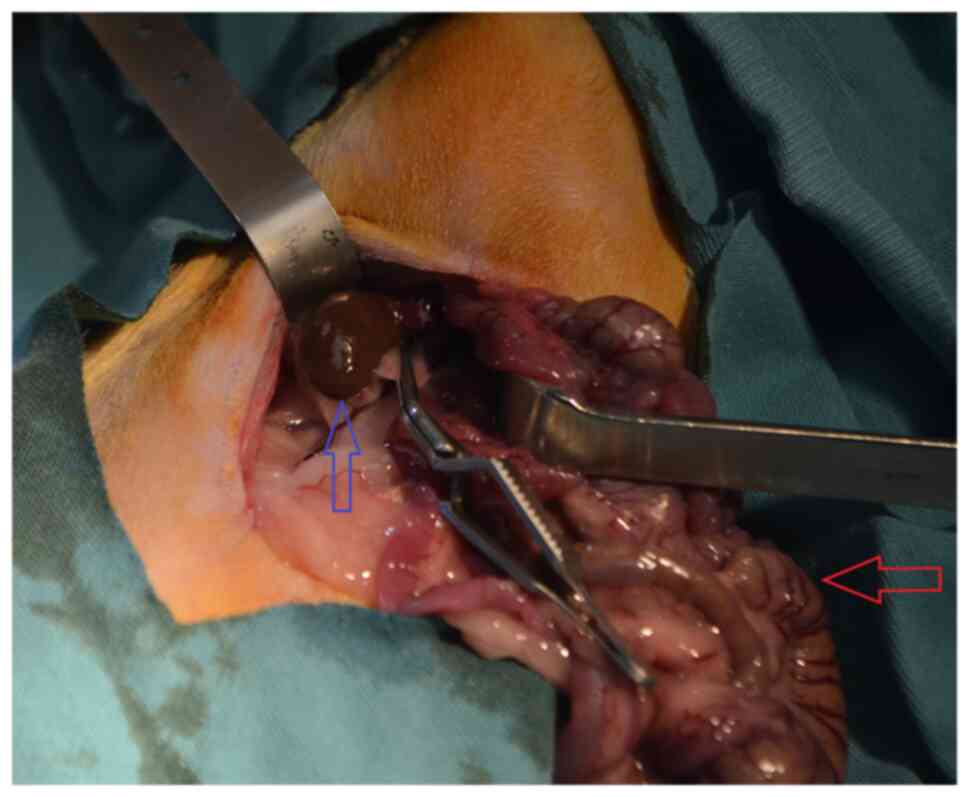

Experimental rat renal ischemia model

Each animal was anesthetized and then placed in a supine position on the surgical table. A 3-cm incision was made through the midline of the abdomen. Renal ischemia was induced in the rats in the I and T groups by bilaterally blocking their renal pedicles, including the renal artery, using atraumatic microvascular clamps for 45 min (Fig. 1). To provide reperfusion following ischemia, the atraumatic microvascular clamps were removed. Subsequently, abdominal incisions were repaired with 3/0 silk sutures in all groups. At the end of the experiment, deep anesthesia was achieved in the rats by confirming that they did not respond to tail clamping following the administration of intramuscularly injected ketamine hydrochloride (50 mg/kg) and xylazine hydrochloride (5 mg/kg; Alfazyne 2%). Subsequently, the animals were euthanized by exsanguination through intracardiac puncture. Death was confirmed by absence of heartbeats determined by listening to cardiac sounds with the use of a stethoscope (27,28). Bilateral nephrectomy was then performed by re-laparotomy. Both kidneys were removed from each animal, with one frozen in liquid nitrogen and kept at -80˚C for further biochemical analysis, whilst the other was preserved in 10% formalin at room temperature for 48 h for histological analysis. The centrifugation of blood samples was performed at 2,110 x g for 10 min at 2-8˚C. Serum was stored in Eppendorf tubes at -80˚C for TNF-α and IL-6 testing after BUN and creatinine levels were measured for the assessment of renal function.

Figure 1

Image of the right renal pedicle being obstructed with an atraumatic microvascular clamp. Blue arrow showing the right kidney and red arrow showing the intestines.